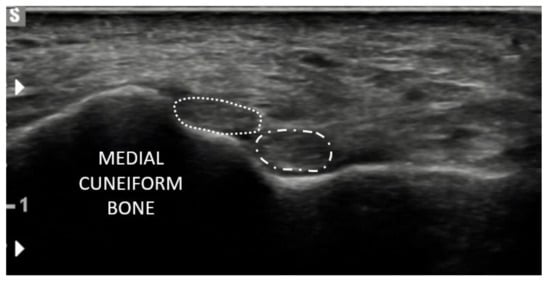

- Olewnik, Ł.; Podgórski, M.; Polguj, M.; Topol, M. A cadaveric and sonographic study of the morphology of the tibialis anterior tendon—A proposal for a new classification. J. Foot Ankle Res. 2019, 12, 1–8. [Google Scholar] [CrossRef] [PubMed]